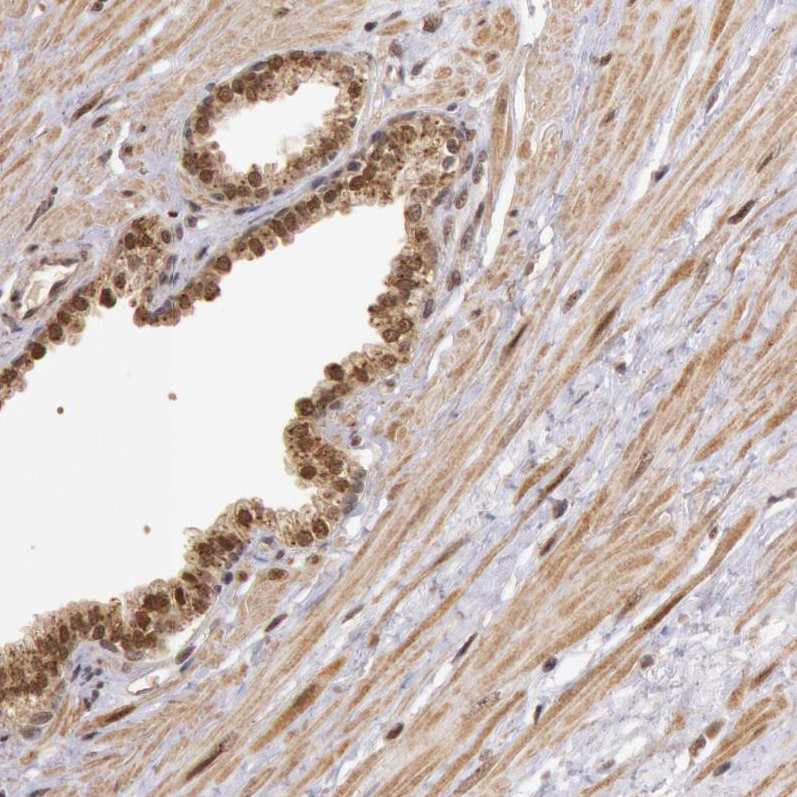

Immunohistochemical staining of human cerebral cortex shows moderate to strong nuclear positivity in neurons.